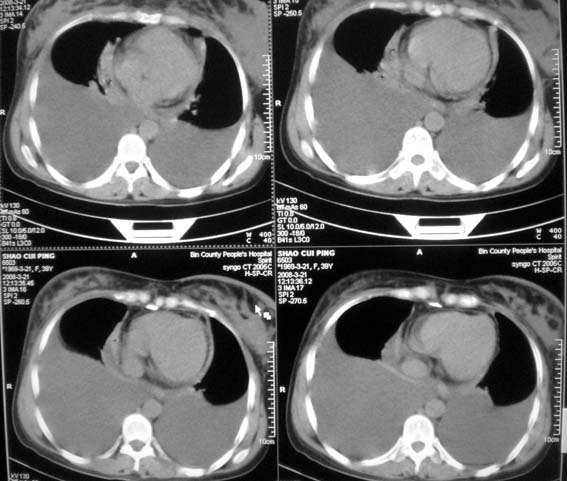

以下是引用zsl6918在2008-3-21 21:41:00的发言:[br]胸腔积液,心包积液,明确性质有难度。常规思路考虑结核性,建议抽液化验明确。

以下是引用卜一在2008-3-22 1:48:00的发言:[br][br] [br] 大量胸腔积液伴肺组织膨胀不全+心包积液。建议行纤支镜! [br] [br]

以下是引用随光逐影在2008-3-21 23:13:00的发言:[br]1)右肺中叶及左肺上叶舌段感染性病变。2)右肺中叶周围型肺癌待排。3)双侧胸腔积液并双下肺部分肺组织膨胀不全。4)心包积液。

以下是引用拾荒者在2008-3-22 21:21:00的发言:[br]胸腔积液、心包积液,双下肺膨胀不全,建议穿刺细胞学检查或抽液后进一步ct检查。